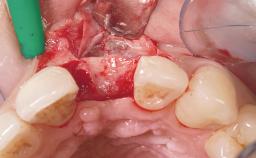

Late Flapless Placement of an Implant in a Maxillary Left Central Incisor Site

A 39-year-old male patient presented with a chief complaint of discomfort and gingival discoloration around his maxillary left central incisor. He was in good general health and was a non-smoker. His past dental history was significant because of the traumatic fracture of tooth 21 in a sporting accident at age 13. Initial dental treatment included endodontic therapy and a full-coverage restoration. The patient became symptomatic 5 years later, when structural failure of the tooth resulted in the dislodgment of the crown. Endodontic retreatment, apical surgery, and post-and-core restoration were performed.

Soft Tissue Grafting Simultaneous

Soft Tissue Contour and Volume Slightly compromised